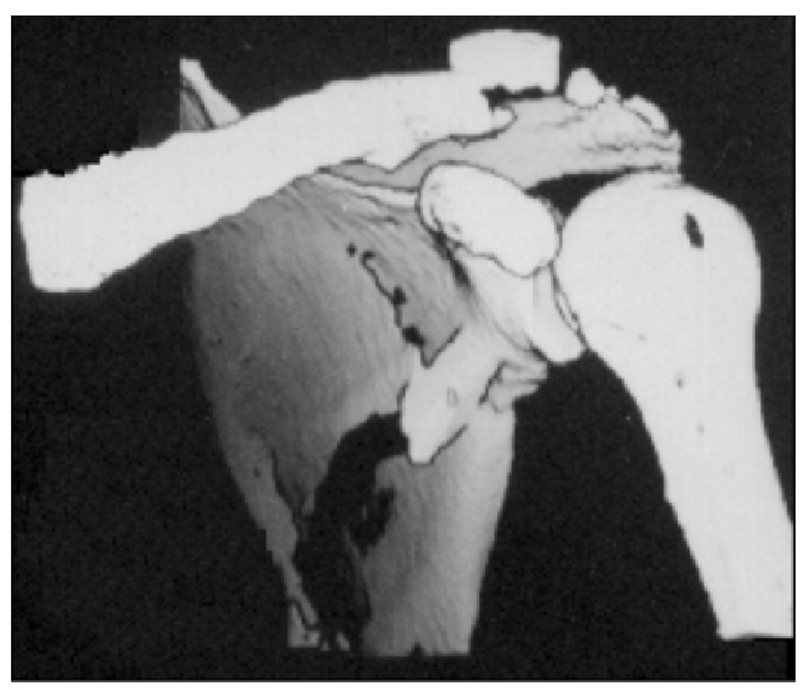

病例2为1例累及肩胛盂、肩胛颈和肩胛骨体部的复杂肩胛骨骨折(图11-12)。

术前设计采用跨骨折区域钢板螺钉固定(图13)。术中可见纵向骨折区域骨质薄弱,骨折粉碎严重,钢板放置位置有限,操作极其困难(图14)。术中采用多块接骨板跨骨折区域固定,术后X线片及三维CT重建显示复位满意(图15)。针对此病例,如果采用缝线辅助固定技术,可使手术操作过程简化,达到同样的固定效果(图16)。

图11 CT三维重建及轴位重建示肩胛骨骨折累及肩胛盂、肩胛颈和肩胛骨体部 图A:CT三维重建;图B:CT轴位重建

图12 CT冠状位重建及手绘示意图重现骨折累及肩胛盂、肩胛颈及肩胛骨体部 图A:CT冠状位重建;图B:手绘示意图